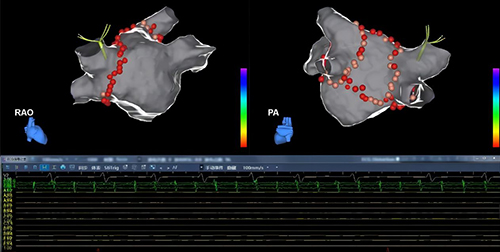

3月9日,贵州医科大学附属医院李伟教授团队周纬教授完成了贵州首例TrueForce压力导管房颤射频消融手术。周纬教授表示微创电生理研发的Columbus三维心脏电生理标测系统结合EasyStars一次性使用星型磁电定位标测导管(以下简称EasyStars星型标测导管),能够精准重建左心房模型和各个肺静脉的走行,为房颤消融提供很好的解剖基础。使用TrueForce微孔灌注压力监测导管进行肺静脉前庭消融,安全且有效地输出射频能量,实现肺静脉电位的单圈隔离及左房“PVI+BOX”线性消融。消融结束后使用EasyStars星型标测导管观察肺静脉和左房后壁的电位,可以清楚地看到电位消失,手术非常成功。“使用微创电生理这一套房颤射频消融解决方案,能提供给术者不输进口品牌的手术体验,有了这一次成功的手术经验,对于房颤射频消融手术中使用国产产品替代进口产品,我们越来越有信心。”周纬教授感叹道。

4月10日,广东省人民医院薛玉梅教授、廖洪涛教授深入广东基层,使用微创电生理自主研发的TrueForce压力导管完成了茂名市和高州市两家中心的房颤射频消融手术,廖教授表达了对TrueForce压力导管的高度认可:“对比进口品牌,TrueForce压力导管整体操控表现优异,使用EasyStars星型标测导管建模,模型饱满美观,结构清晰,提供了非常稳定而且优秀的临床体验。以后会在基层医院的手术中大力推荐国产房颤解决方案。”